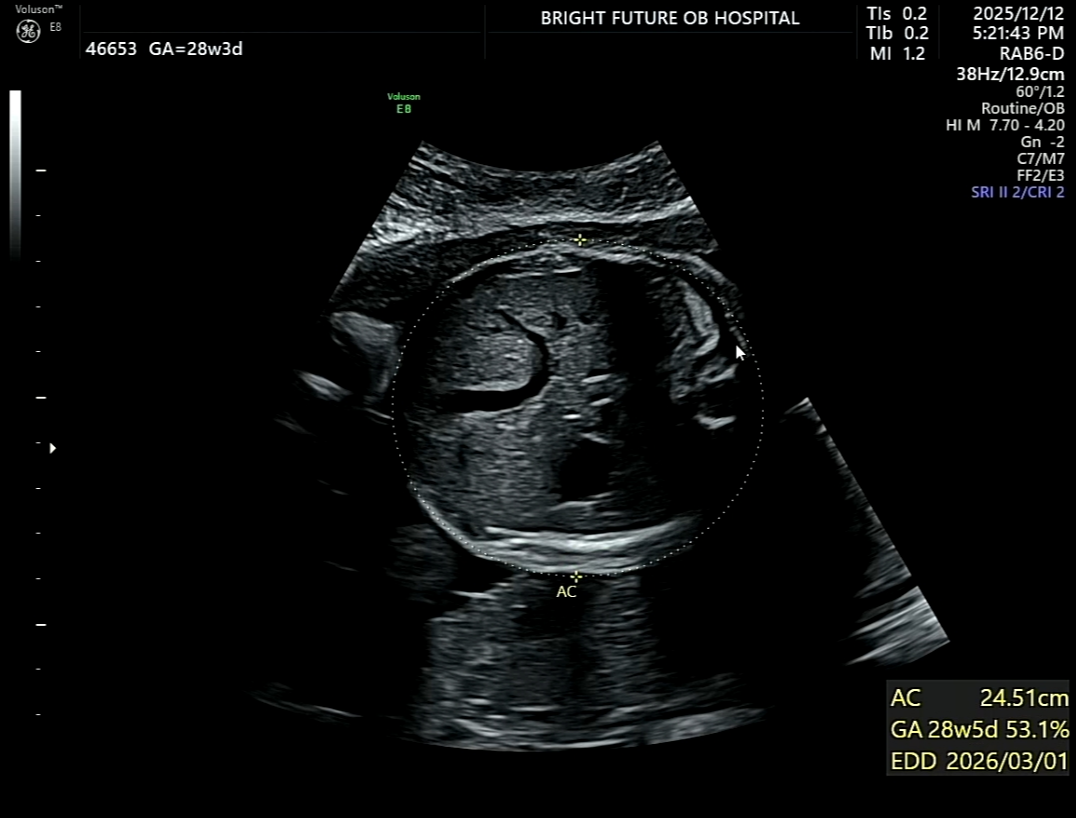

허벅지 길이 늘어나다!

그동안 허벅지 길이(FL)가 늘 1주 정도 작게 나와서

은근히 신경이 쓰였던 것도 사실이다.

어디서 “단백질을 많이 먹으면 도움이 된다”는 얘기를 듣고

그 이후로 고기를 정말 열심히 먹었다.

그래서일까?

이번 검사에서는 주수보다 하루 빠른 허벅지 길이라는 결과를 받았다.

괜히 혼자 뿌듯해지는 순간.

다만 늘 그렇듯,

머리 크기와 배둘레는 주수보다 조금 큰 편이었다.